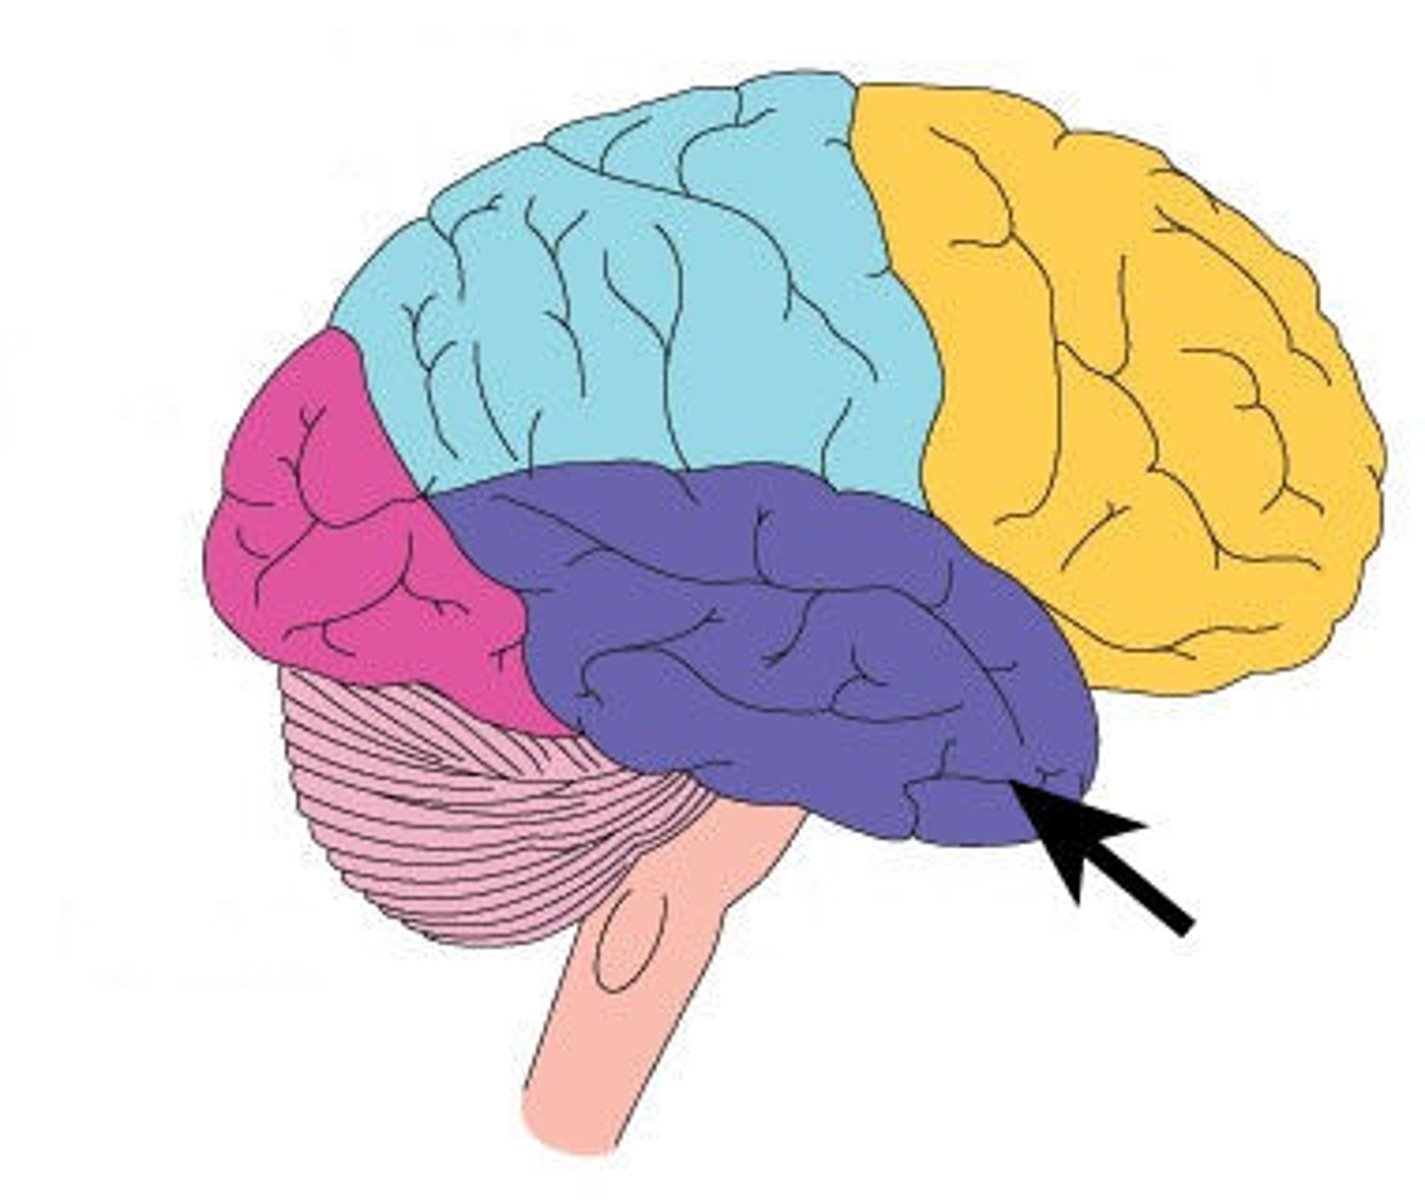

central sulcus

between postcentral and precentral gyri

longitudinal fissure

separates cerebral hemispheres

frontal lobe

associated with social cues, personality, planning, movement, emotions, and problem solving - contains primary motor cortex

precentral gyrus

primary motor cortex

parietal lobe

A region of the cerebral cortex whose functions include processing information about touch, contains primary somatosensory cortex

postcentral gyrus

primary somatosensory cortex

occipital lobe

visual center

temporal lobe

language centers, auditory processing, olfactory